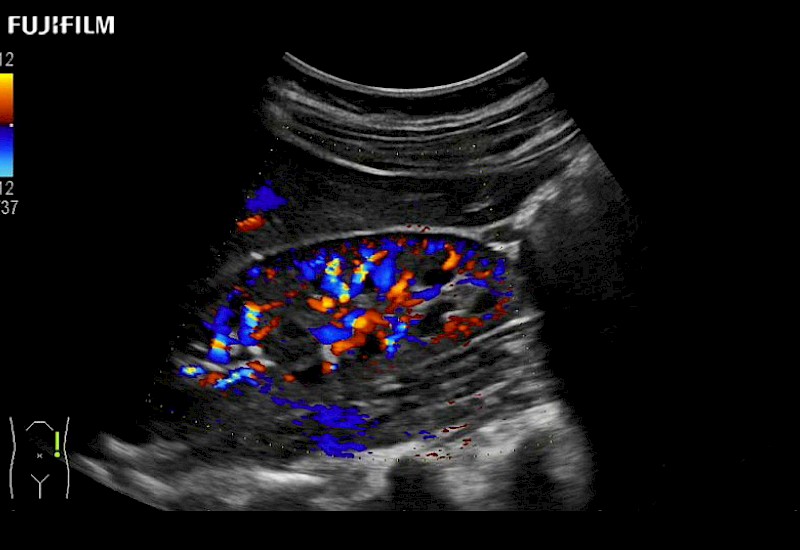

Our dedication to Laparoscopic Surgery allows us to offer superior image quality, outstanding system reliability and intuitive use of cutting edge technology.